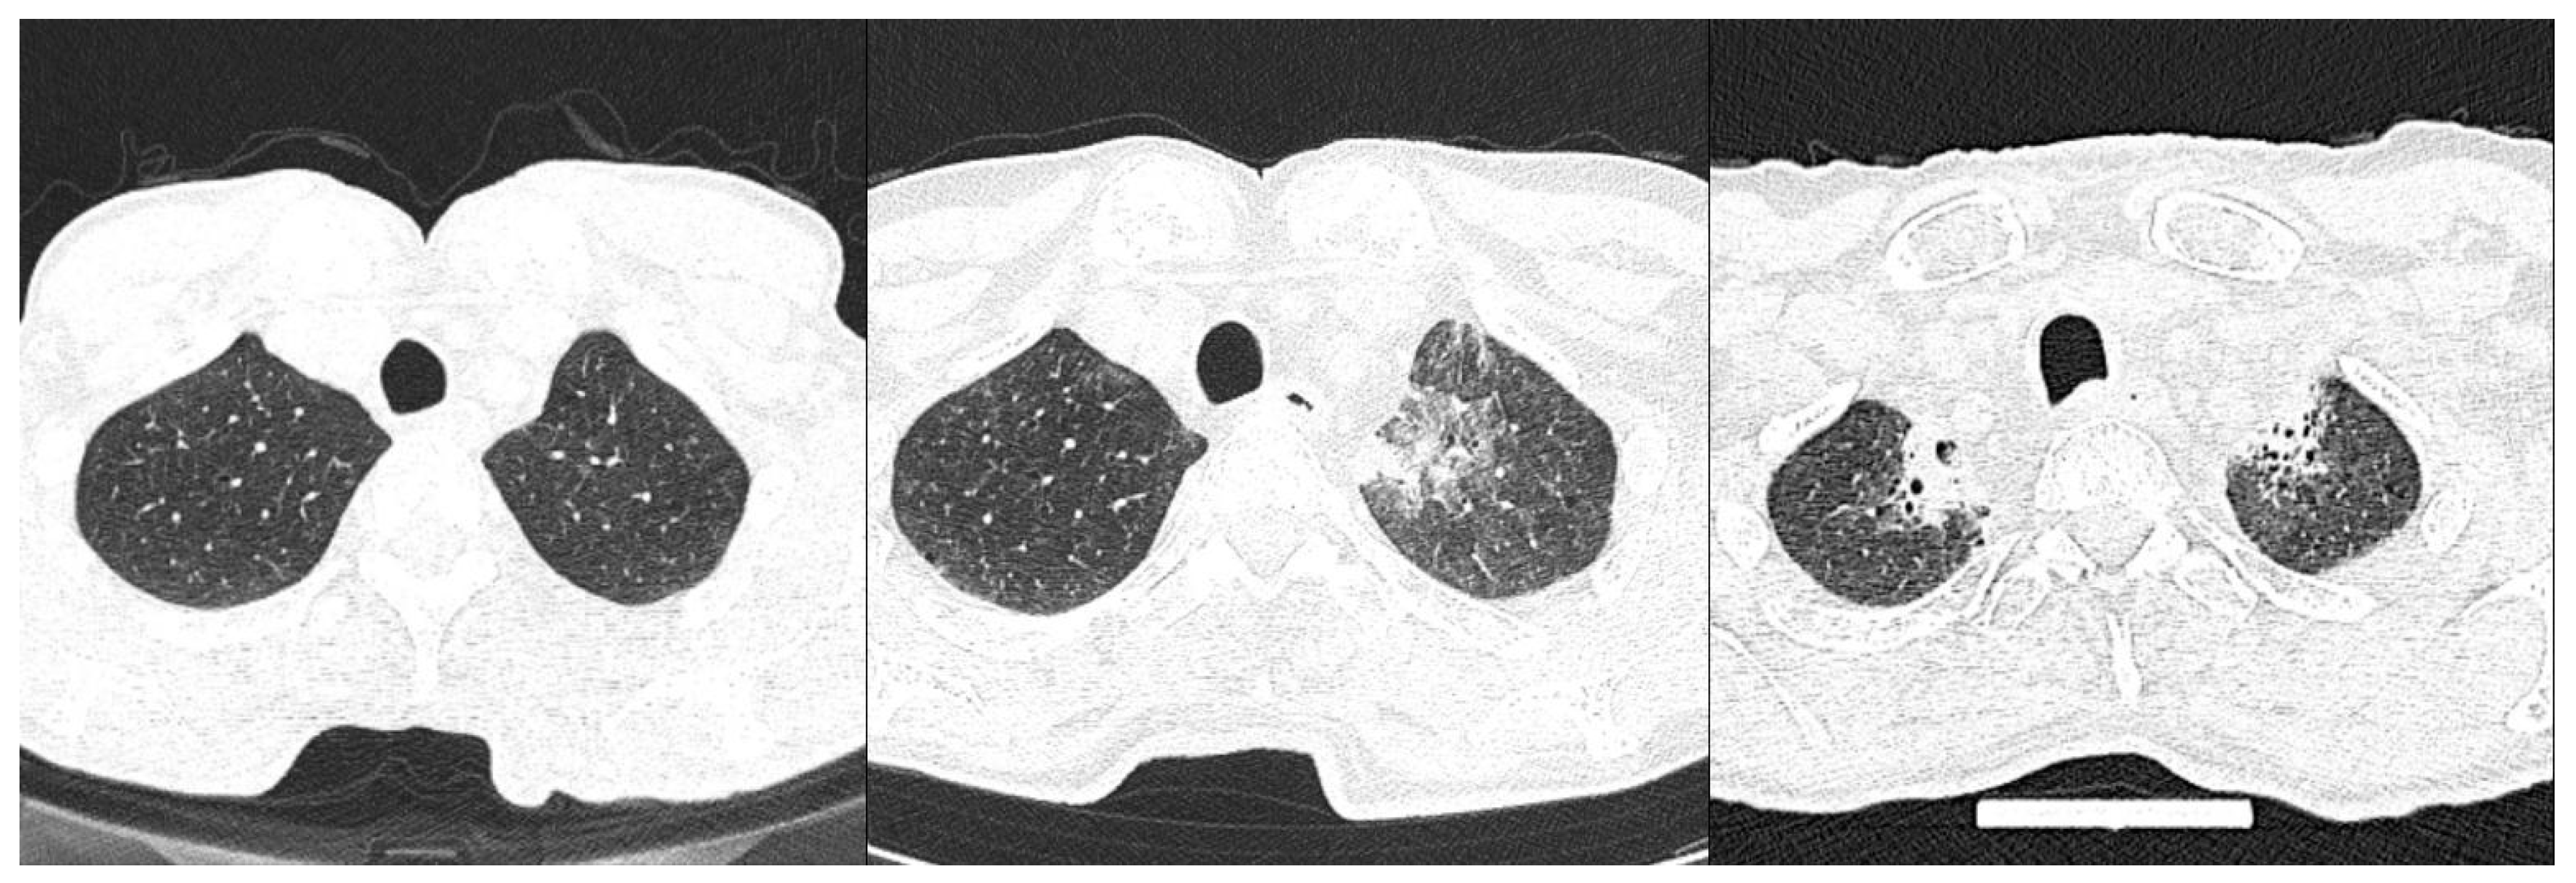

Out of 65 patients with an available follow-up lung MSCT, 21 patients received adjuvant radiotherapy of regional lymph nodes (60Gy in 30 fractions) after initial surgical resection. There was statistically significant difference in radiation-induced fibrosis in the upper lung zones after adjuvant radiotherapy in the ILA compared to non-ILA group (Table 6, Figure 6).

Figure 6.

Axial MSCT scans of lung parenchyma in patients with HNSCC and reported ILA changes in lower lung zones after adjuvant radiotherapy, demonstrating (left to right): upper lung zone prior to treatment showing no abnormality; following acute radiation injury of lung shown as GGO; thickened intralobular and interlobular septa; and finally fibrous consolidations with architectural distortion in the last picture.

Newly developed lung changes in the upper lung zones, described as radiation-induced lung fibrosis, were a more frequently described radiological finding after the use of adjuvant radiotherapy of regional lymph nodes in the ILA group. Radiation pneumonitis is described as an acute manifestation of radiation-induced lung disease with consequential radiation-induced pulmonary fibrosis if not resolved [19]. Although the images within the interval of 3 months after receiving radiotherapy were not available for the analysis and assessment of acute radiation-induced changes, more frequent incidence of fibrosis in the upper zones might be an indicator that the occurrence or extent of post-radiation changes is related to ILA changes in patients with HNSCC. There is some evidence that ILA, in fact, may contribute to post-therapy changes in the lung parenchyma. Numerous studies have revealed ILA changes to be an independent risk factor for worsening post-treatment outcomes in lung and esophageal malignancies.